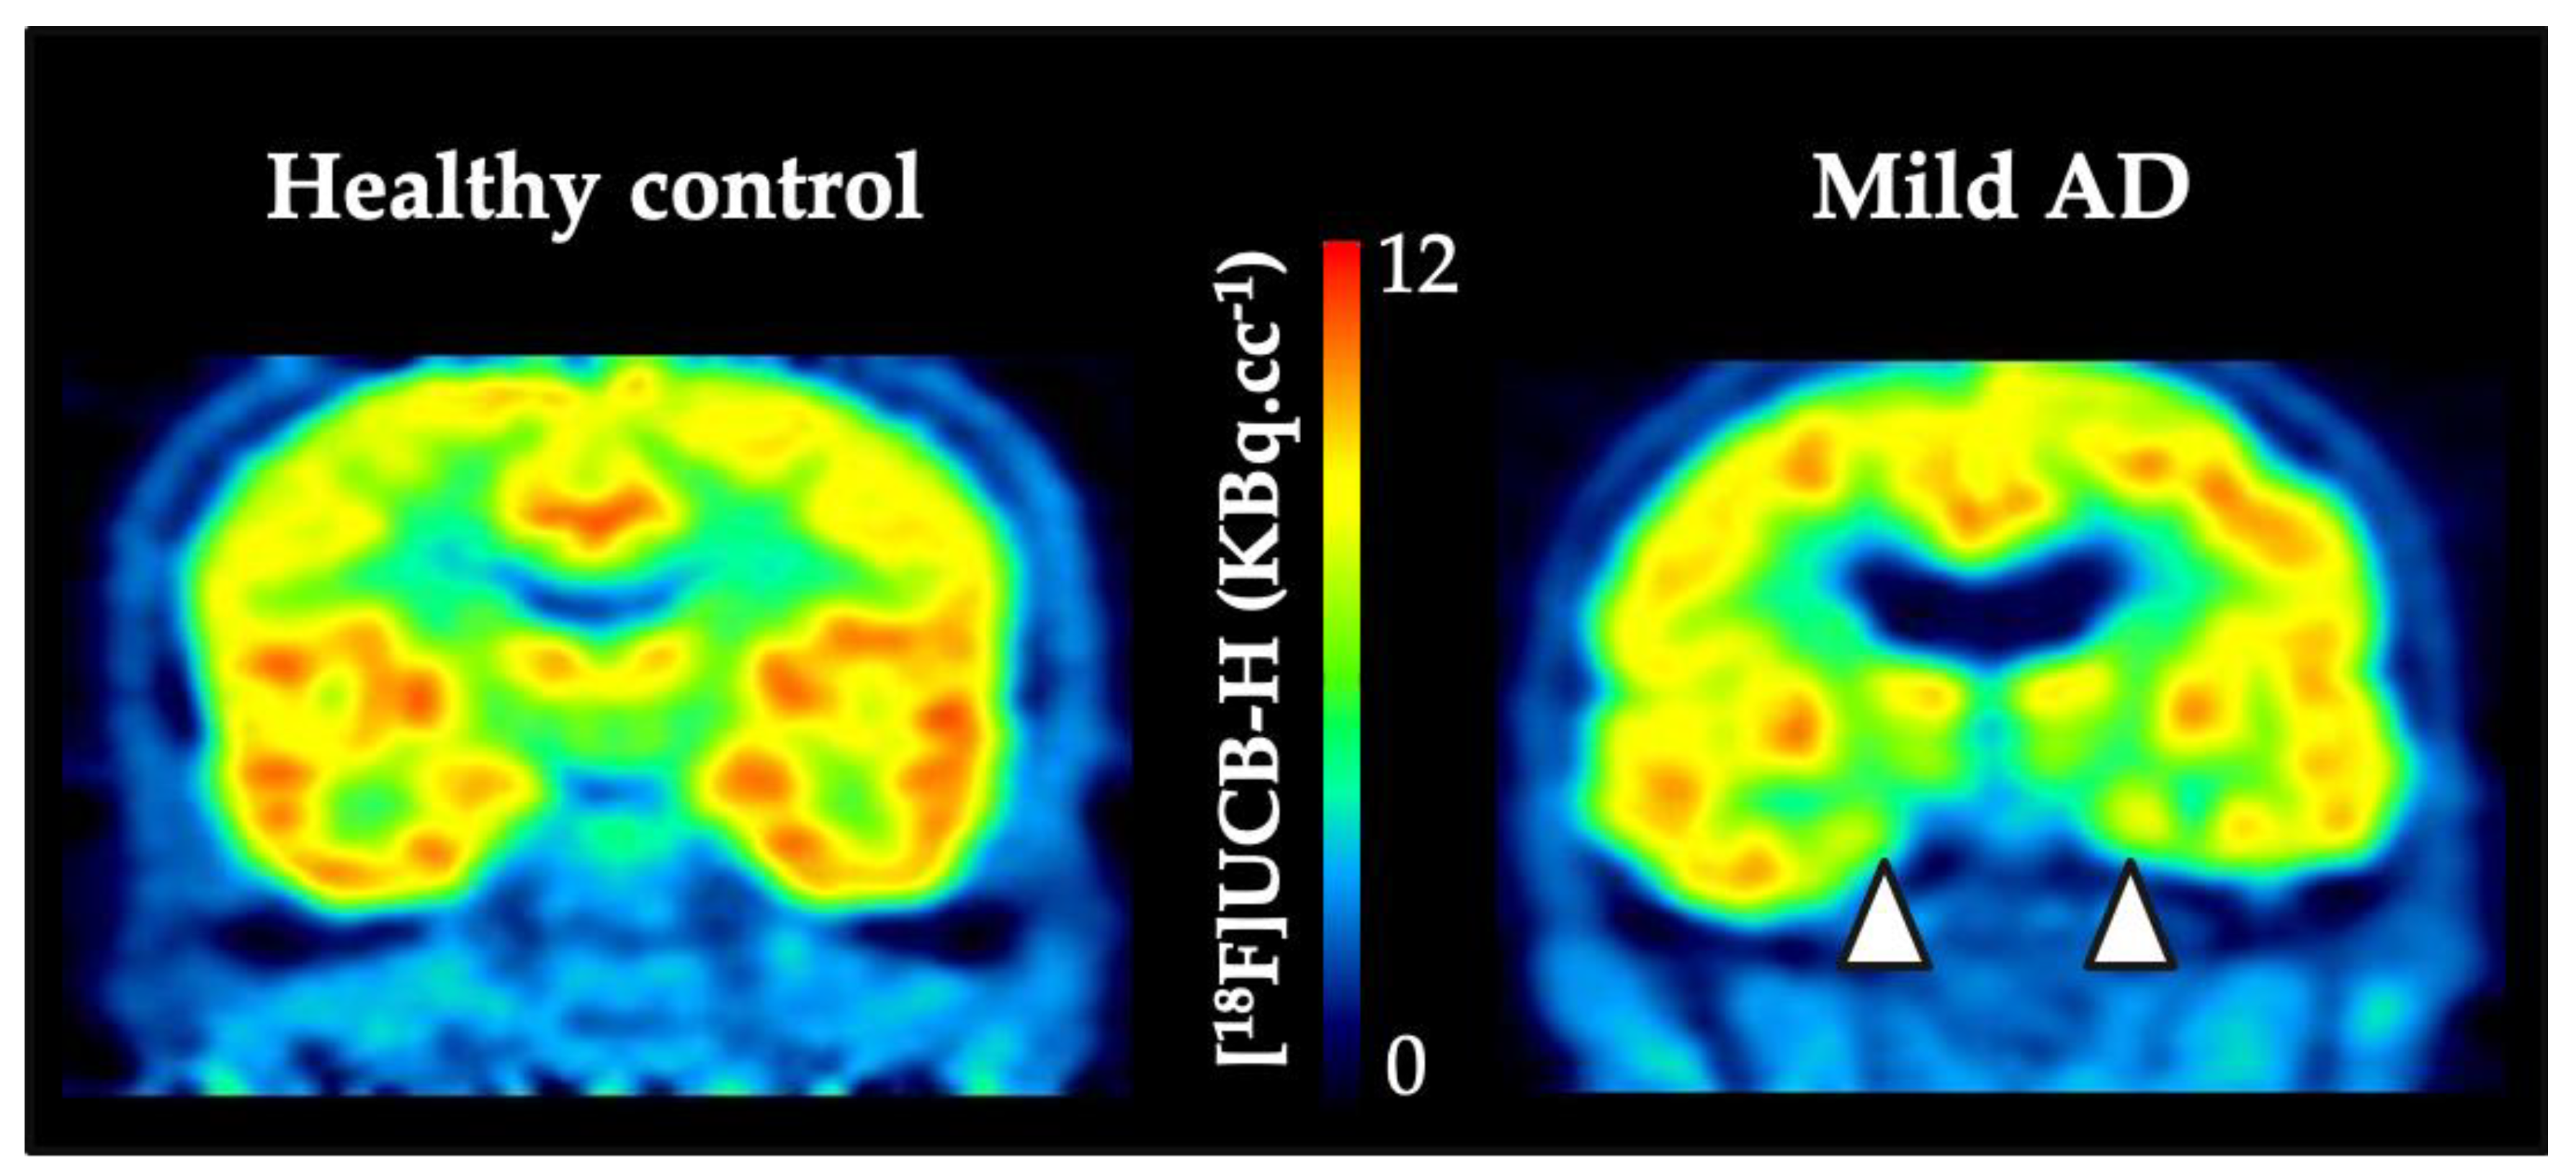

- Bahri, M.A.; Plenevaux, A.; Aerts, J.; Bastin, C.; Becker, G.; Mercier, J.; Valade, A.; Buchanan, T.; Mestdagh, N.; LeDoux, D.; et al. Measuring brain synaptic vesicle protein 2A with positron emission tomography and [18 F]UCB-H. Alzheimer’s Dementia: Transl. Res. Clin. Interv. 2017, 3, 481–486. [Google Scholar] [CrossRef] [PubMed]

- Bastin, C.; Bahri, M.A.; Meyer, F.; Manard, M.; Delhaye, E.; Plenevaux, A.; Becker, G.; Seret, A.; Mella, C.; Giacomelli, F.; et al. In vivo imaging of synaptic loss in Alzheimer’s disease with [18F]UCB-H positron emission tomography. Eur. J. Nucl. Med. Mol. Imaging 2019, 47, 390–402. [Google Scholar] [CrossRef]